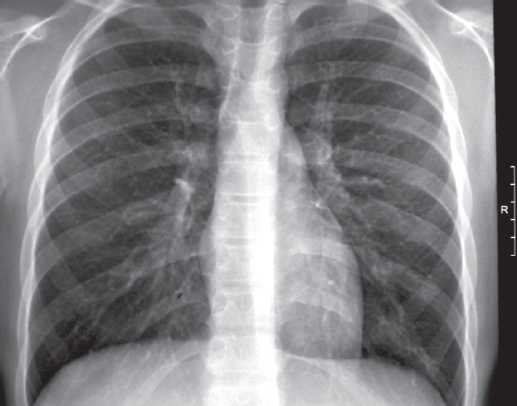

С 07.06.2012 начато лечение ОЛЛ по программе ALL–MB-2008. Ребенок получал дексаметазон, винкристин, рубомицин на фоне массивной антибактериальной терапии (меропенем, амикацин, флуконазол). Отмечались осложнения: нейтропения, токсическое поражение печени, почек, полинейропатия, язвенно-эрозивное поражение пищевода с положительной динамикой на фоне проводимой терапии. Ремиссия достигнута к 36-му дню терапии ОЛЛ (12.07.2012). Миелограмма на 36-й день терапии. 12.07.12: ядерность костного мозга 40,0 · 109/л, бласты — 0,4 %. Проведены курсы консолидации 1, 2, 3. Состояние ребенка улучшилось, контрольное МСКТ-исследование легких 27.06.2012 выявило положительную динамику рассасывания инфильтративных изменений в легочной ткани, плеврального выпота. Однако в связи с появлением хрипов в легких 19.07.2012 выполнена контрольная МСКТ грудной клетки, на которой обнаружено появление множественных двусторонних очагов в легких (рис. 3).

Рис. 3. Пациент, 6 лет. Компьютерная томография грудной клетки 19.07.2012: появление множественных двусторонних очагов в верхних отделах легких

Fig. 3. Patient, 6 years old. Chest computed tomography 19.06.2012: the appearance of multiple bilateral foci in the upper lungs

20.07.12 проведена фибробронхоскопия со взятием бронхоальвеолярного лаважа (БАЛ). Исследование БАЛ на МБТ: полимеразная цепная реакция двукратно, микроскопия и посев отрицательны. Микроскопия и посев БАЛ на грибы выявили Aspergilla niger, диагностирован инвазивный аспергиллез. Проведен курс терапии противогрибковым препаратом вориконазолом с положительной динамикой клинической и лабораторной. МСКТ: контрольное обследование 21.08.2012 — без патологических изменений в легких. Всего на отделении гематологии ДГБ № 1 ребенок находился с 31.05.2012 по 06.02.2013 (с перерывами). Весь этот период мальчик наблюдался фтизиатром, получал противотуберкулезную терапию: изониазид (с 08.06.2012 по 25.10.2012), пиразинамид (с 08.06.2012 через день по 25.10.2012), этамбутол (08.06.2012–23.07.2012 через день), ПАСК (24.07.2012–28.10.2012). 25.10.2012 установлено клиническое излечение туберкулеза, перевод в группу III-Б диспансерного учета.